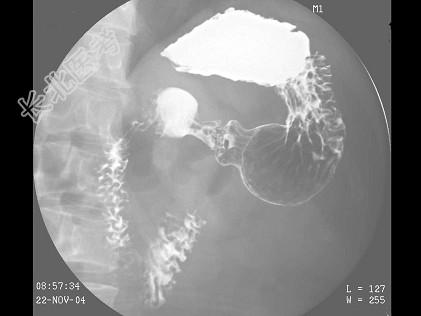

- 多项选择题女,49岁, 进食上腹痛,腹部肠胀气近2天, 今肛门已排气,大便已解, 结合图像,最可能的诊断为 ( )

C、胃溃疡

D、球部溃疡

E、胃粘膜脱垂